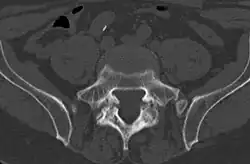

Cross-sectional image of a vertebra showing spondylolysis.

Commonly known as a CT Scan or CAT scan, this form of imaging uses x-rays to produce multiple cross-sectional images, or "slices", through a part of the body. This allows a physician to evaluate the body in greater detail than an x-ray allows. For this reason the CT scan is much more accurate in detecting spondylolysis than an x-ray. Bone scintigraphy combined with CT scan is considered the reference standard, which means that it is best at detecting spondylolysis.[16][18]